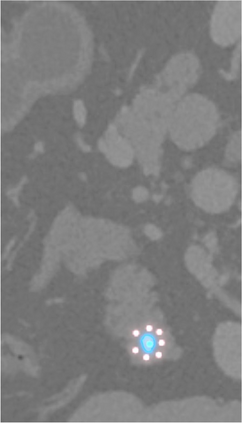

Creating large-scale and well-annotated datasets to train AI algorithms is crucial for automated tumor detection and localization. However, with limited resources, it is challenging to determine the best type of annotations when annotating massive amounts of unlabeled data. To address this issue, we focus on polyps in colonoscopy videos and pancreatic tumors in abdominal CT scans; both applications require significant effort and time for pixel-wise annotation due to the high dimensional nature of the data, involving either temporary or spatial dimensions. In this paper, we develop a new annotation strategy, termed Drag&Drop, which simplifies the annotation process to drag and drop. This annotation strategy is more efficient, particularly for temporal and volumetric imaging, than other types of weak annotations, such as per-pixel, bounding boxes, scribbles, ellipses, and points. Furthermore, to exploit our Drag&Drop annotations, we develop a novel weakly supervised learning method based on the watershed algorithm. Experimental results show that our method achieves better detection and localization performance than alternative weak annotations and, more importantly, achieves similar performance to that trained on detailed per-pixel annotations. Interestingly, we find that, with limited resources, allocating weak annotations from a diverse patient population can foster models more robust to unseen images than allocating per-pixel annotations for a small set of images. In summary, this research proposes an efficient annotation strategy for tumor detection and localization that is less accurate than per-pixel annotations but useful for creating large-scale datasets for screening tumors in various medical modalities.